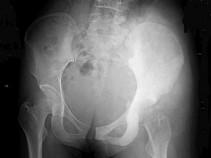

问题 16岁女性患者,左臀部疼痛伴发热2个月,X线检查如图所示,最佳的诊断是 ( )

选项 A、左髂骨网状细胞肉瘤 B、左髂骨软骨瘤 C、左髂骨急性化脓性骨髓炎 D、左髂骨软骨肉瘤 E、左髂骨成骨肉瘤

答案 E